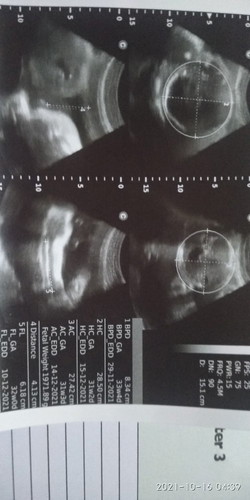

Bunda semua mau tanya kemaren sya usg 28 Minggu Uda keliatan kelaminnya laki" tpi kemaren USG lgi 33 Minggu kenapa bisa jadi prmpuan... Alhamdulillah nggak di sngka... Suami minta pr terkabul.... Tpi syanya mlh kaget kog bisa berubah soalnya Uda jelas banget low kalo anaknya laki".... Tpi kemaren yg prtama suami belum prcya kalo anaknya laki" mie di buktikan lagi trnyata prmpuan.... Keajaiban tuhan. #seriusnanya .. ya Allah terima kasih atas karuniamu...